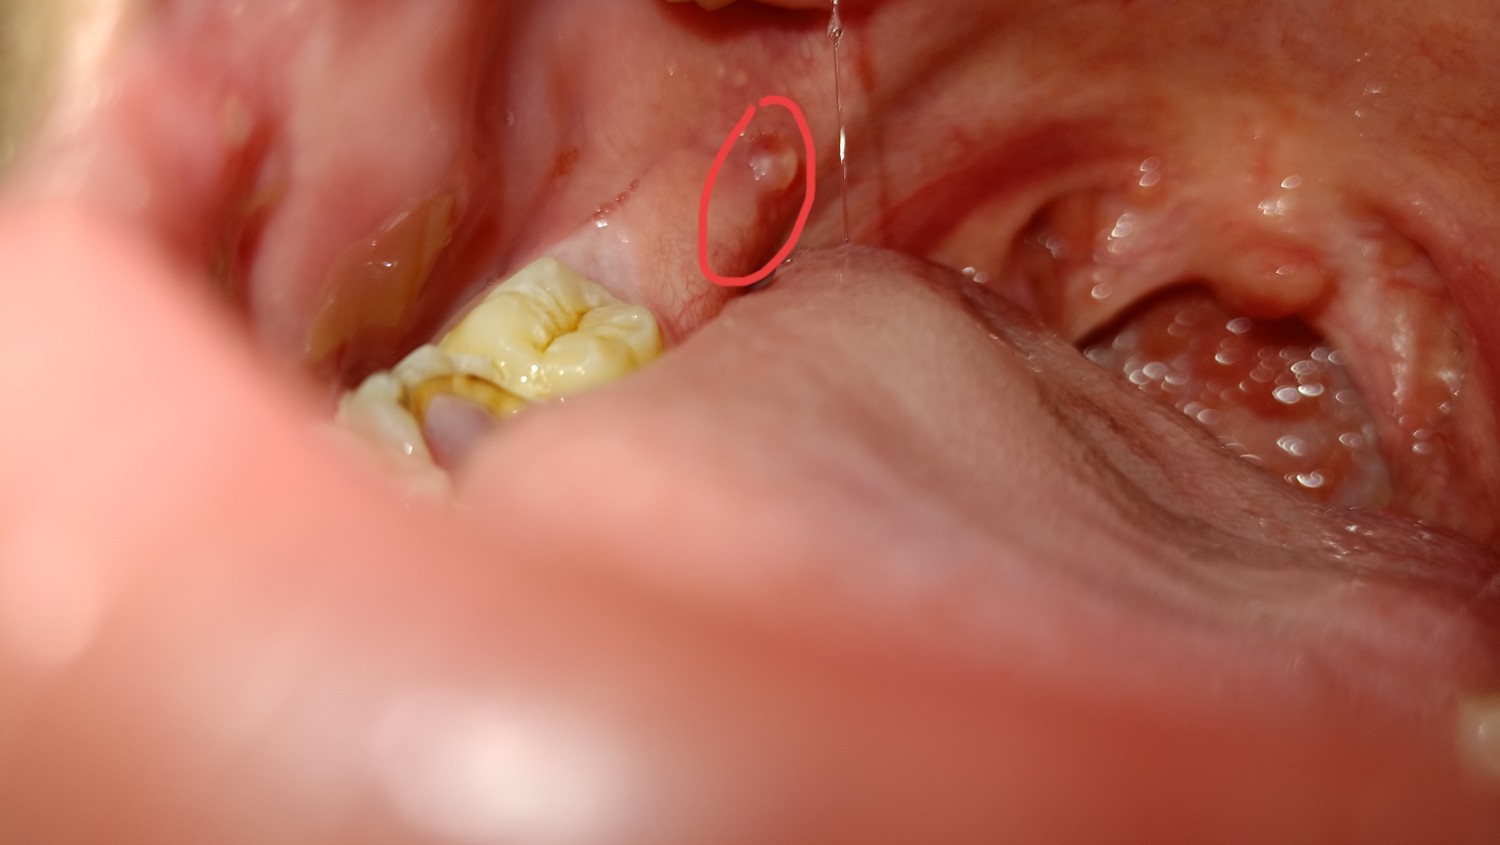

มันคือตุ่มอะไรครับในปาก มันเป็นตุ่มใสเรียบนูนออกมาตอนผมทานข้าวเสร็จพิดีกลัวว่าเป็นมะเร็งช่องปาก